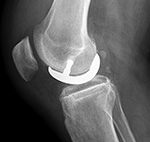

| Posterior cruciate retaining total knee arthroplasty (TKA) |

A PCL-retaining knee allows for preservation of the posterior cruciate ligament and is a relatively unconstrained design (figure: cruciate retaining TKA). For this type of prosthesis to be successful there must be good bone stock, intact surrounding muscles and ligaments, and a posterior cruciate ligament that remains functional (Mulcahy, 2013).